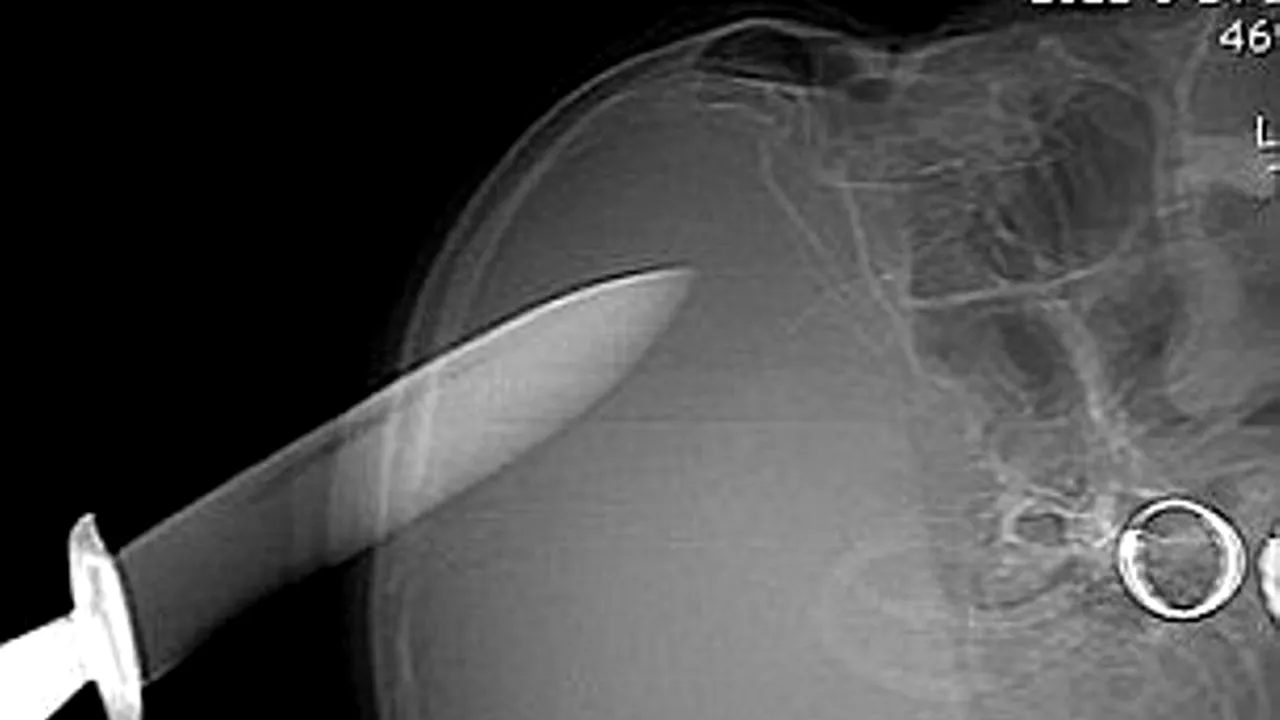

O femeie din China a supraviețuit incredibil după ce și-a înfipt în cap un cuțit cu lamă de 12 centimetri. Femeia era cunoscută ca suferind de afecțiuni psihice, iar incidentul s-a petrecut într-un moment în care nu era supravegheată, scrie Daily Mail.

Când a fost descoperită, ea a fost dusă imediat la spital însă medicii au redirecționat-o către o unitate medicală aflată la peste 100 de kilometri, cadrele medicale temându-se să o opereze pe motiv că daunele provocate ar putea fi foarte mari.

Femeiea a ajuns peste trei ore la un spital în care a fost operată și spre surprinderea tuturor s-a refăcut foarte repede, peste cinci zile fiind externată/